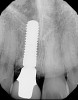

Fig 11. Radiograph of healed implant site No. 8 at 3 months.

Figure 11

Plugging into digital workflows provides opportunities to integrate CAD/CAM technologies at every step of the treatment process for dental implants. In another example, a patient presented with a failing tooth No. 8 (Figure 6 and Figure 7). After discussing treatment options, the patient chose to forgo any treatment to address tooth and soft-tissue asymmetries and wanted to proceed with a dental implant-supported restoration without additional treatment. After integrated 3-dimensional planning, the tooth was extracted, and then an implant and the final custom CAD/CAM abutment (titanium base with zirconia supra-structure) were placed with a provisional restoration in the same visit (Figure 8 and Figure 9). Soft-tissue grafting was also done at the same visit to address the deficient buccal tissue height on No. 8 (Figure 10). At 3 months, the patient presented for the final restoration, with excellent healing around the implant (Figure 11) and soft-tissue healing guided by the custom abutment (Figure 12).